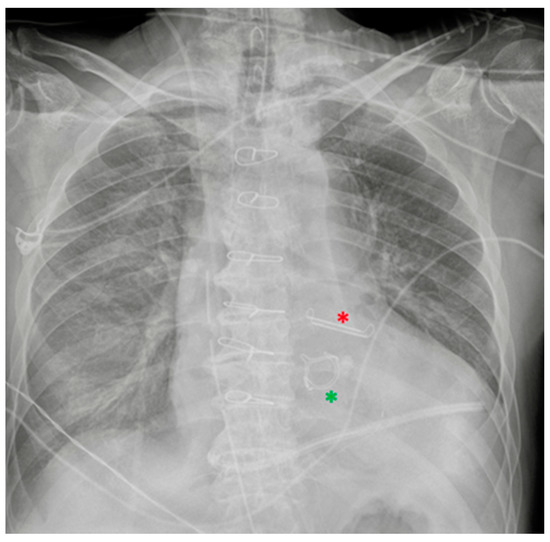

| Nasogastric tubes | Proximal (oesophagus)/distal (duodenum) * misposition Coiling/kinking Insertion into the respiratory tree → aspiration pneumonia Gastric wall perforation Intracranial insertion (rare) * |